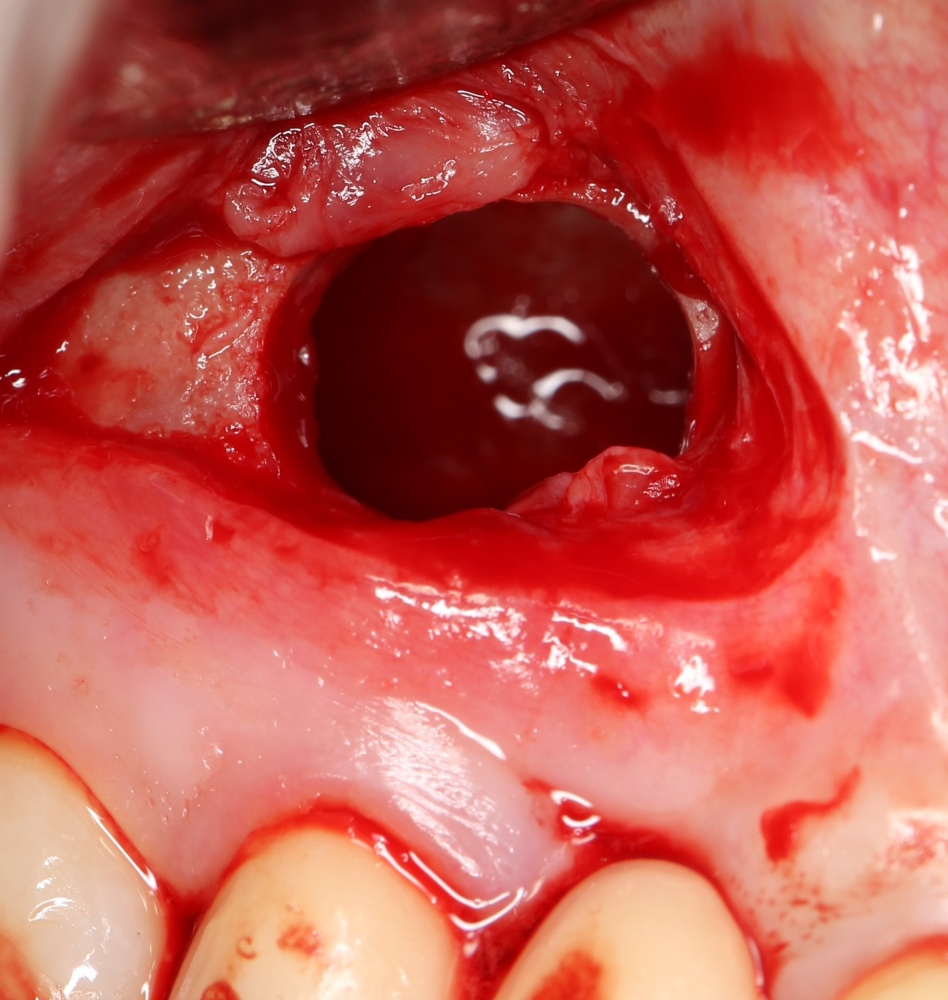

Я зафиксировал костный блок практически без адаптации на несколько винтов. Обрати внимание, что винты находятся в зоне, где не планируется установка имплантатов. Фиксация должна быть надежной, поскольку мне еще предстояла подготовка лунок для имплантатов. Трех винтов для этого вполне достаточно.

Дальнейшая адаптация костного блока свелась к сглаживанию острых краев. После чего я приступил к подготовке лунок и установке имплантатов.

Установка имплантатов.

Напомню, что для этой работы я выбрал субкрестальные имплантаты Ankylos C/X. Они прекрасно сочетаются с любым методом остеопластики.

Глянем на то, что получилось:

Осталось адаптировать костный блок (убрать острые края), проверить его фиксацию и, при необходимости, добавить винты. Десятисекундное дело.